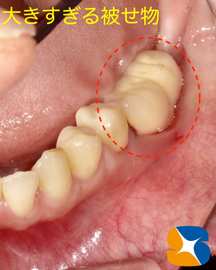

お口の中を拝見すると、かなり大きな被せ物がインプラントの支柱に接続されていることが伺えます。

このように異常に大きな被せ物を装着されてしまうと、なかなか上手くブラッシングは出来ません。